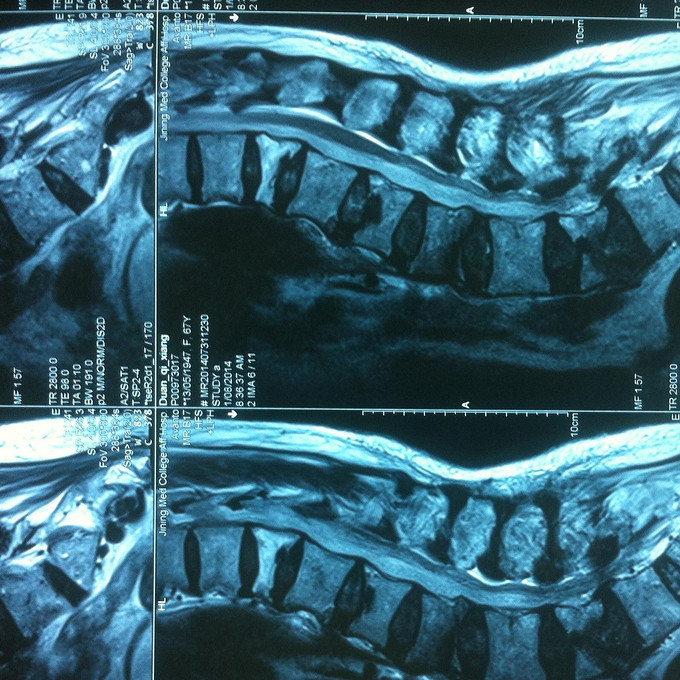

查体:腰部活动受限,腰骶部叩痛明显,体位试验阳性,双下肢感觉无减退,双侧屈髋、伸膝、踝背伸、踇背伸、跖屈肌肌力4-5级,双侧膝腱反射++,跟腱反射+,双侧巴氏征阴性。 辅助检查: X-ray:骨质疏松,腰3、5楔形变,MR:骨质疏松,腰3、5新鲜骨折